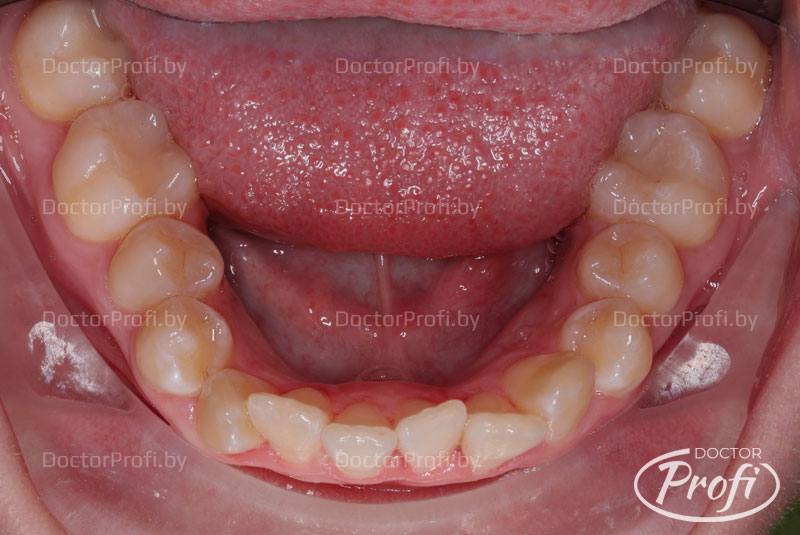

Исправление одностороннего дистального прикуса и чрезмерного наклона зубов

Пациентка обратилась в клинику с жалобами на неэстетичный зубной ряд. На консультации у ортодонта были выявлены следующие проблемы с прикусом: односторонний дистальный прикус, протрузия (избыточный передний наклон) передних зубов.

До